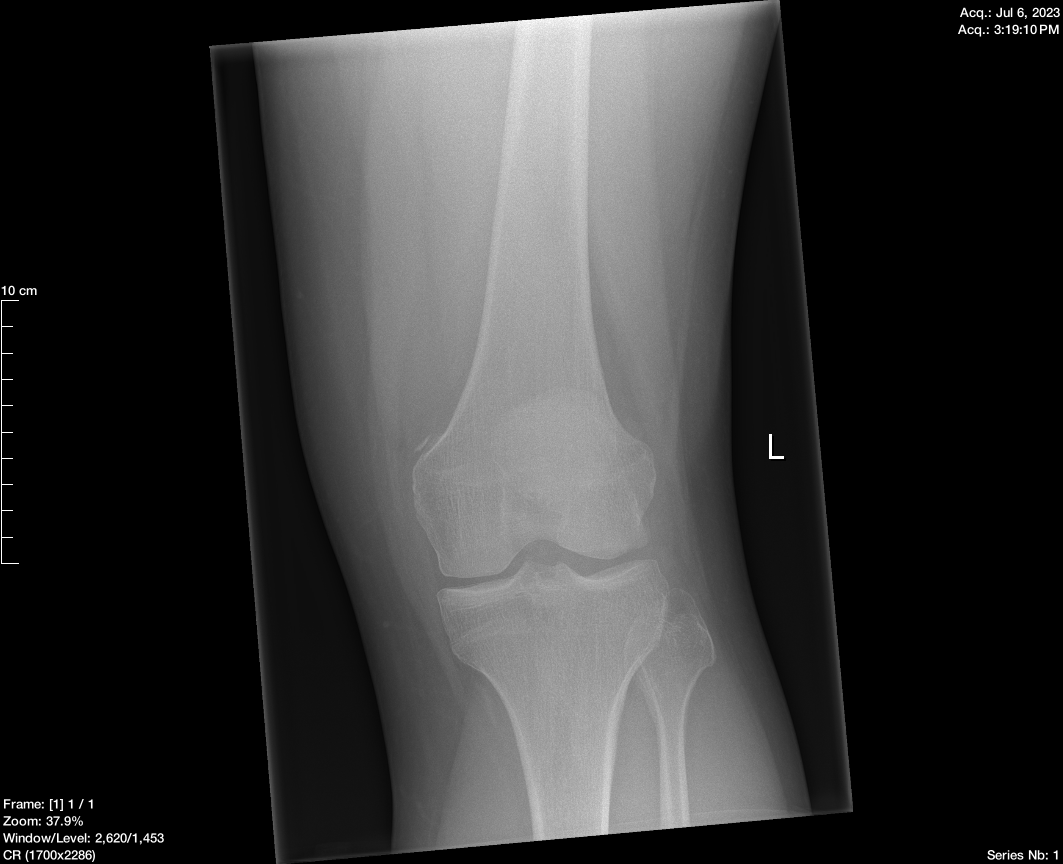

Coronal

The report from the radiologist was that everything looked fine apart from a small piece of bone that had chipped off.

- Fracture/Dislocation: No acute fracture or dislocation identified.

- Joint Effusion: Moderate effusion in the suprapatellar bursa.

- Lipohaemarthrosis: Not present.

- Pellegrini-Stieda Lesion: Ossification at the proximal medial aspect of the medial femoral condyle, likely due to a previous avulsion fracture or ligamentous injury.

- Additional Density: Seen in the posterior femorotibial joint on the HBL view but not on AP view.

- Nature of Density: Unclear if degenerative or an old avulsion injury; not appearing acute.

At this point, I was a bit gutted they hadn’t found anything because I knew something was wrong. Because of clinical presentation, the doctor referred me to the orthopaedic department for further investigation.